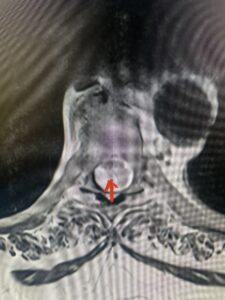

This 67-year-old female presents with progressive heaviness and numbness of the legs and difficulty ambulating. Her right leg was worse than her left. She had right greater than left hip flexor weakness. She was hyperreflexia in her lower extremities. An MRI (Fig. 1) demonstrated an intradural arachnoid cyst at T10-11 with severe spinal cord compression. She also appeared to have an arachnoid cyst above from T4-T8 with anterior displacement and compression of the spinal cord. Because of her severe myelopathy and the findings on MRI the patient underwent laminectomy for surgical decompression of cyst. Intraoperatively the focal arachnoid cyst at T10-11 appeared as a small bubble crushing the spinal cord anteriorly with scarring of the arachnoid with no CSF flow above or below.

Fig. 1b Axial T2-weighted thoracic MRI demonstrating spinal cord compression from T10-11 arachnoid cyst (red arrow)